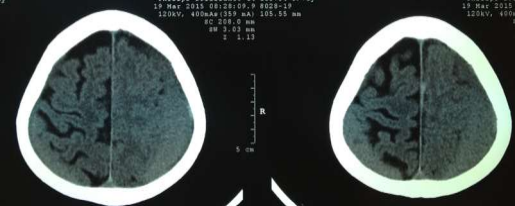

Radiology

Fig 1,2,3,4,5,6,7,8,9,10,11,12,13,14,15

Thirty eight out of Eighty-two patients were treated conservatively and were studied (25 men; 13 females, mean age, 64.8 years). The average thickness of the hematoma was 18 mm, the mean midline shift was 4.7 mm, and the average attenuation value of bleed on computed tomography scan was 33.5. Thirty-eight were treated successfully with steroid treatment, whereas 44 patients required surgery. The female gender, less midline shift, less density (Hounsfield units) was noted to be associated with successful medical treatment. We propose a grading based on the total score given to the midline shift and density.

3. Hypo dense or isodense subdural collection on CT-scan.

Figure 1

Figure 2

Figure 3

Figure 4

Figure 5

Figure 6

Figure 7

Figure 8

Figure 9

Figure 10

Figure 11

Figure 12

Figure 13

Figure 14

Figure 15